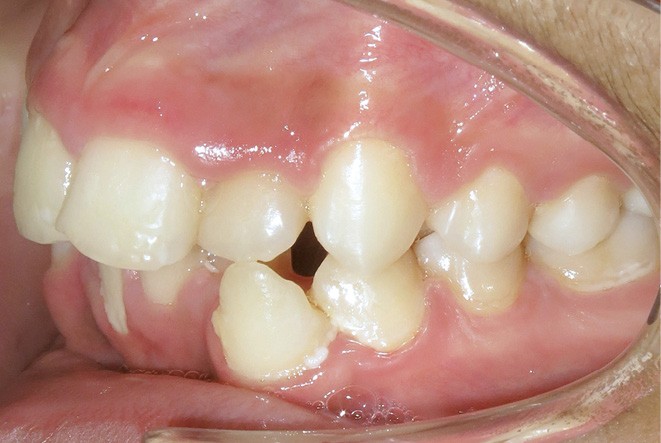

Le niveau d’hygiène est alarmant, car le rituel du brossage des dents n’est pas instauré dans la famille. Des caries se sont développées sur les dents temporaires et en ont imposé l’extraction. Les molaires permanentes ont dérivé mésialement, réduisant l’espace disponible sur l’arcade.

En denture adulte, la DDM est majeure avec un déficit de place estimé de 13 mm à la mandibule. Les lésions carieuses ont aussi touché les premières molaires permanentes maxillaires. La 26 a été avulsée et la 27 a pris sa place. Côté controlatéral, la 16 est fortement délabrée, rendant impossible sa conservation. Les molaires ayant plus mésialé à l’arcade mandibulaire, les rapports occlusaux sont de classe III. Les incisives sont versées vers l’avant, mais nous pouvons considérer qu‘il s’agit d’une biproalvéolie ethnique. Du point de vue squelettique, le patient présente une classe II squelettique par rétromandibulie sur un schéma facial hyperdivergent (fig. 1a-j).